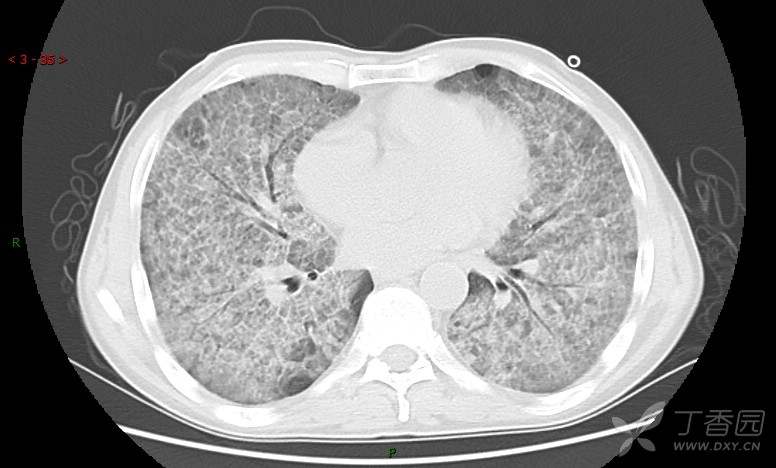

地图+铺路石征=PAP?那升高的CEA怎么说(病例3连发,附其他2例链接)

患者男,42岁,咳嗽半年余,加重伴憋喘2月余。

患者半年余前无明显诱因出现间断咳嗽,干咳为主,偶咳少量黄白痰,剧烈咳嗽或运动后可出现轻度憋喘,无高热、脓臭痰,无胸痛、咯血及晕厥,无低热乏力及盗汗,无心前区压榨感及夜间阵发性呼吸困难,初未在意,未予正规诊治。2月余前患者自觉上述症状较前加重,咳嗽、憋喘明显,黄白色粘痰略有增多,伴有发热,热前伴有畏寒、寒战,体温最高达38.9℃,先后就诊多家医院,入住重症监护室,未行气管插管,考虑“重症肺炎”,给予“美罗培南、复方磺胺甲噁唑”等药物抗感染,“卡泊芬净”抗真菌,并给予“甲泼尼龙”等药物治疗35天,经治疗后症状好转于2018-04-02出院。患者自出院后仅应用中药治疗(具体不详),并给予家庭氧疗,平素仍有间断咳嗽,咳少量黄白色粘痰,活动后憋喘明显,活动耐量差,以卧床为主。

肺内弥漫性网状结节影,PET-CT却无阳性病灶,这是?(附其他2例链接)